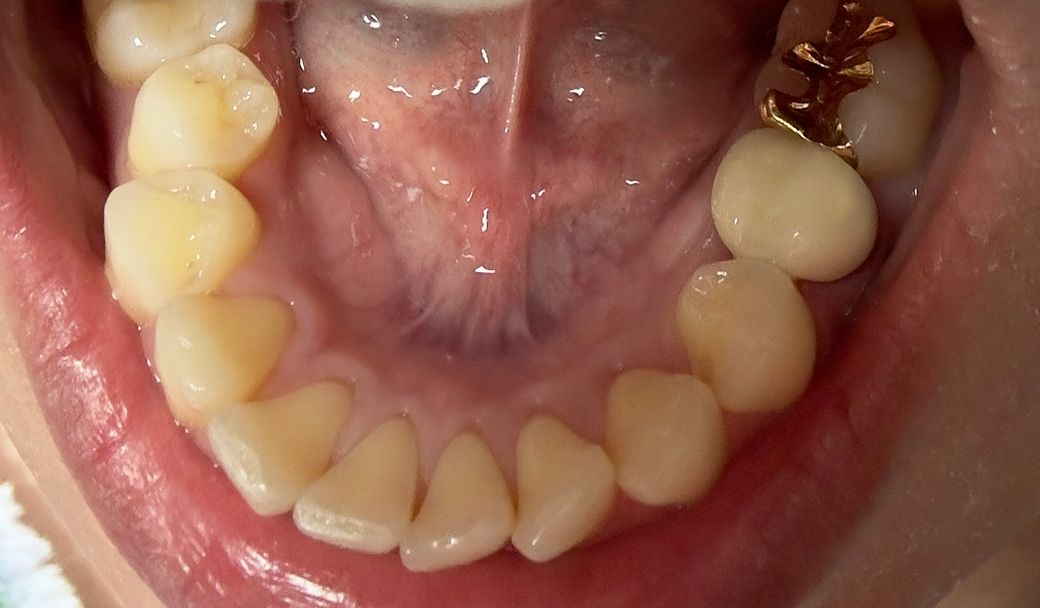

치아 아래 앞니 잇몸퇴축이 심한가요?

원래는 없었는데 아랫니 치아 사이 공간이 생긴거 같아요. 아랫니 안쪽에서보면 치은퇴축이 더 심한거 같은데 교정도 하지않았는데 이정도면 심한건가요?

• 1번 째 사진

치아 퇴축의 정도가 심해보이지는 않습니다. 구강관리 잘해주시면 문제가 될 것은 없어보입니다.

이정도의 잇몸 상태는 정상적인 것으로 보입니다. 안쪽 바같쪽 다 정상적인 것으로 보입니다. 각 치아마다 잇몸 높이는 조금씩 다릅니다.

잇몸퇴축 심하지 않습니다. 잇몸 색상 등 잇몸 건강 상태도 나쁘진 않습니다. 다만 치열이 고르지 않아 그 틈을 잇몸이 다 채워주지 못했습니다.

사진상으로 보면 잇몸퇴축이 심해보이진 않아 보입니다. 지금처럼 잇몸관리를 해주시면 크게 문제가 되진 않을것같습니다.